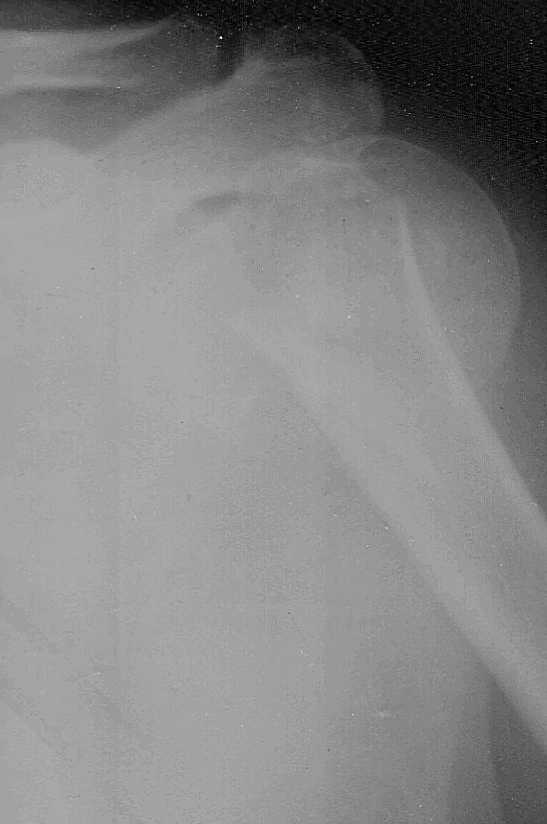

Доброго времени суток,коллеги.Больная 51 год травма 2,11,09 в 20:00 сосудистых,неврологических расстройств нет

3,11,09 выполнена попытка закрытой репозиции,безуспешно. Планируем накостный синтез Т-образной пластиной.Буду крайне признателен за дельные советы.

хотелость бы посмотреть вторую проекцию, а вообще, в чём проблема? Тактика леченния подобных переломов достаточно подробно описана во многих руководствах, как в русских, так и в зарубежных. Может какой то подвох? ;)

Phylos отличная, но очень дорогая пластинка. В данном случае, скорее всего, можно обойтись LPHP. Хотя, информации по одной проекции может оказаться недостаточно. КТ при таких переломах должна быть рутинным исследованием.

Ну зачем вторая проекция, ради академизма? Такие переломы приводят к смещению дистального отломка вперед и вверх, вызывая, иногда, угрозу перфорации кожи. Поэтому, как можно быстрее чем-нибудь прооперировать - хоть пучком спиц, Т-, L- образной пластиной, никелидом титана и т.п. Эта зона "неприхотлива" для сращения. А пока вы ждете от дельруса нумелок или филос - внутренний пролежень будет!

Не, не в академизме дело ;) лет пять назад интораоперационно нашёл фрагмент головки под большой грудной мышцей науровне средне-ключичной линии (на прямых снимках примерно такого же качества не было и подозрений на это) И фрагмент тот был весьма приличных размеров , около 30 % головки. Казуистика? может быть, но чем больше информации перед операцией, тем лучше планирование, не так ли?